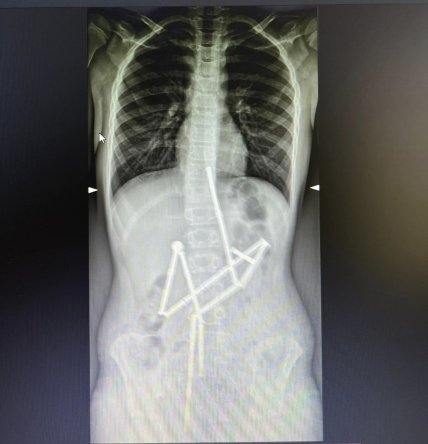

Специалисты "Охматдета" спасли ребенка, который проглотил 20 элементов магнитного конструктора. Все детали находились в разных частях желудочно-кишечного тракта, однако были соединены между собой.

На рентген-снимках специалистам удалось увидеть 20 магнитных элементов, которые находились в разных частях желудочно-кишечного тракта и при этом были соединены между собой.

Консилиумом врачей было принято решение о проведении неотложной операции, так как каждый час ожидания мог ухудшить состояние пациента. Сложность залючалась в том, что все проглоченные магнитные элементы были сцеплены между собой.

К счастью, опытным специалистам удалось захватить первый магнит и извлечь его вместе с цепочкой из 18 элементов конструктора.

Не смотря на это один магнит остался в брюшной полости и специалисты не могли удалить его эндоскопически. Ребенку была проведена операция, в ходе которой хирурги обнаружили пять перфоративных отверстий и последний элемент конструктора. Все отверстия были закрыты, а магнит удален.